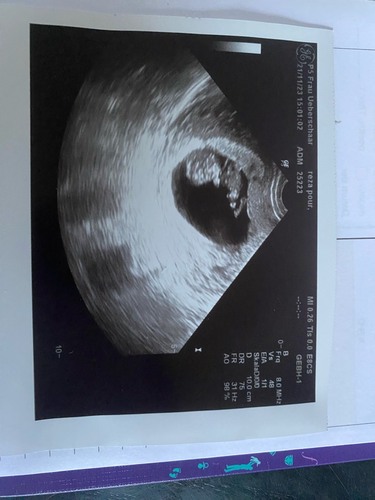

Unser Mäuschen hat total rumgeturnt während der Untersuchung 😍 es hat sich an der Gebärmutter abgedrückt und ist rumgehupft und auch in die Luft geboxt, es war einfach herrlich zuzuschauen. Unser ET wurde 10 Tage vorverlegt 😁😁❤️ sind sehr happy. Hoffe nur noch der NIPT ist unauffällig 🙏

Achja wir sind von 10+6 auf 12+2 gerutscht... Plötzlich im 2. Trimester od ...